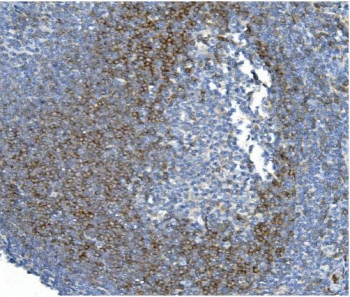

CD79b molecule, immunoglobulin-associated beta, also known as CD79B (Cluster of Differentiation 79B), is a human gene. By fluorescence in situ hybridization, It is mapped to 17q23.3. The CD79B protein together with the related CD79A protein, forms a dimer associated with membrane bound immunoglobulin in B-cells, thus forming the B-cell antigen receptor (BCR) which is a multimeric complex that includes the antigen-specific component, surface immunoglobulin (Ig). CD79b also can enhances phosphorylation of CD79A, possibly by recruiting kinases which phosphorylate CD79A or by recruiting proteins which bind to CD79A and protect it from dephosphorylation.